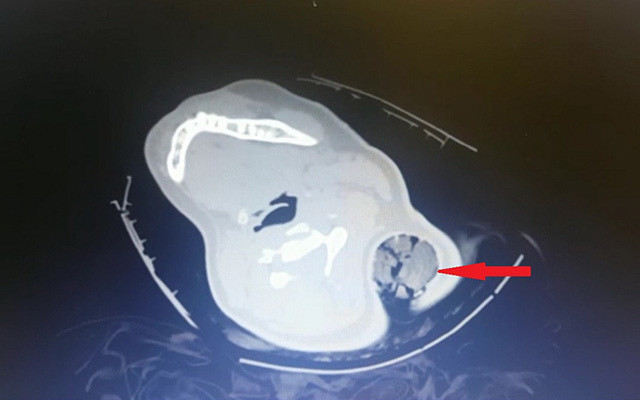

Ağır yaralanan genç kız, vücuduna saplanan tahta kazık ile Kahramanmaraş Sütçü İmam Üniversitesi (KSÜ) Sağlık Uygulama ve Araştırma Hastanesine götürüldü. Hastaneye bilinci açık olarak giden B.Ö.'yü görenler, Ortopedi ve Travmatoloji Anabilim Dalı Öğretim Üyesi Dr. Bülent Güneri'ye haber verdi. Hastanın yanına gelen Güneri, çekilen tomografi görüntülerini inceledikten sonra genç kızı ameliyata aldı. Yaklaşık yarım saat süren ameliyatla tahta kazık çıkarılırken, kazığın sinir ve damarlara zarar vermemesi nedeniyle mucize eseri hayatta kalan genç kız olayı bir kaburga kırığı ile atlattı. B.Ö., hastanede gördüğü bir haftalık tedavi sonrası sağlığına kavuşarak taburcu edildi.

Ameliyat öncesi ve sonrasında yaşananları anlatan Dr. Bülent Güneri, telefonuna gelen fotoğrafları görünce şaşırdığını söyledi. Bu tür vakalarda genellikle sinir ve damar yaralanmalarının olduğunu ancak bu olayda sinir ve damar yaralanmasının olmayışının çok ilginç olduğunu ifade eden Güneri, "Hastayı acil ameliyata aldık. Ameliyat esnasında göğüs cerrahi hocamız ve kalp damar cerrahı bölümünden hocamız hazır bulundular herhangi bir komplikasyona yönelik olarak. Ameliyathanede yaptığımız değerlendirmeden sonra anestezi altında yaklaşık 30 santimetrelik tahta bir kazık çıkardık hastadan. Kazık, hastanın saçlarını dolayarak boynundan girip sol kol altından çıkmıştı. Ve böyle kirli bir yaralanma, ev dışında, sokakta olan bir yaralanma enfeksiyon açısından oldukça risklidir. Ama ameliyat esnasında yaptığımız girişimler ve titizlikle uyguladığımız antibiyotik tedavisi sayesinde hastamızda bir enfeksiyon meydana gelmedi" diye konuştu.

"Tıp literatüründe benzer yaralanmalar var, metal ve tahta cisim saplanmaları görülüyor. Ancak bu şekilde boyundan girip koltuk altından çıkan bir cisim yaptığım taramalarda tespit etmedim. Ancak literatürde bildirilen vakalarda çok ciddi sinir yaralanmaları ya da omuriliğe saplanıp da enfeksiyona yol açan bu nedenle tedavi görmek zorunda olan hastalar mevcut. Bizim hastamızda herhangi sinir veya damarsal yapıya denk gelmedi ancak bir kaburga kırığına yol açtı ve içeride bol miktarda hastanın saç bulunduğu için bizi daha çok uğraştıran içeride bulunan saç parçalarıydı. Biz, kazığın gidiş yönü boyunca açmayıp, kazığı ters yönde çıkartıp içeriye bol miktarda steril sıvıyla yıkama uyguladık ve iyi bir antibiyotik tedavisi verdiğimizi düşünüyorum. Bu sayede de bir sorun meydana gelmedi. Hasta oldukça talihli bene, birçok kişi bunu mucize olarak değerlendirebilir. Beni ve ekibimi oldukça şaşırttı. Ve hastayı birlikte değerlendiren cerrahi branştan diğer hocalarımızı da oldukça şaşırttı. Adeta mucize gibiydi diyebilirim."